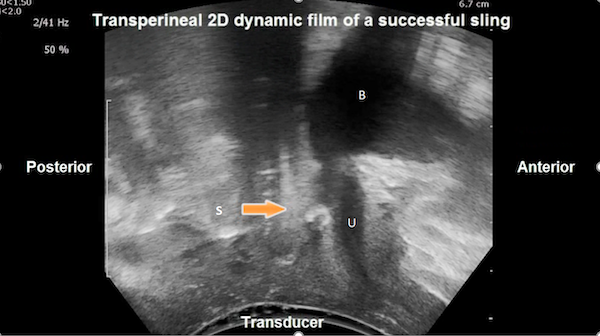

Dynamic Assessment of Sling Function

The question that arises is whether there are other ancillary factors that interact with the sling location to ensure continence, especially during dynamic stress like coughing, sneezing, etc. What explains successful outcomes in the small proportion of patients in our study in whom the sling was located proximally and yet reported cure? In an unmatched case-control study of 100 patients returning for their 1ā2-year follow-up, we determined, using 2D and 3D transperineal ultrasound studies (Hegde et al 2017), that there are three parameters that interact to ensure success:

3. Concordance of urethral movement with the sling during maximal Valsalva: If the sling location on maximal Valsalva relative to the urethral length was identical to that at rest, the urethra was considered to move concordant with the sling (Hegde et al 2017; Figures 4a and 4b). If the sling location on maximal Valsalva relative to the urethral length differed from that at rest, the urethral movement in relation to the sling was considered discordant (Hegde et al 2017; Figure 7).

The best outcomes following mid-urethral transobturator sling surgery as well as TVT sling surgery were found to be associated with concordance of urethral movement with the sling and mid-urethral location at maximal Valsalva followed by deformability of the sling on dynamic assessment (Hegde et al 2014). However, the three parameters often work together to compensate for the failure of an individual parameter to ensure successful outcome (Hegde et al 2014). A patient in whom the sling does not deform on Valsalva (i.e., does not curve into a C-shape from flat at rest along its width) may still have a successful outcome if the sling is in the correct location (mid-urethral) at rest and the urethra moves in a concordant manner with the sling (Hegde et al 2014).